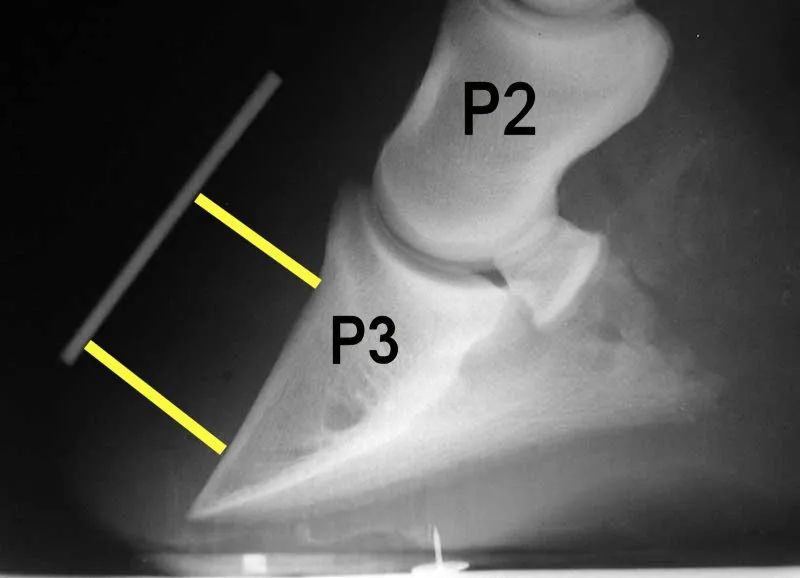

这听起来已经很疼了,但拆开马蹄还有更多惊吓。马蹄后的骨头叫做蹄骨,有点像一块削尖的三角形刀片。

从侧面看,马的蹄骨就像刀刃一样锋利。图片来源:wikipedia马蹄和后面的蹄骨之间全靠一种类似瓦楞纸的组织做支撑。这种一层一层折叠状的组织叫做蹄叶,它其实是由一种特殊的表皮细胞构成的,能够分散蹄骨戳下来的压力。

正常的蹄叶(左红)和长期发炎(蹄叶炎)的蹄叶(右红)。图片来源:见水印也就是说,马其实是一种“刀锋战士”,而给马蹄缓冲的全靠皮肤。

这种情况持续下去,蹄骨就会插破蹄壁,插入蹄叶,马就很容易患上一种非常棘手的疾病——蹄叶炎(laminitis)。英国赛马管理局的兽医学教授 Tim Morris 解释道,骨折的马很容易患上蹄叶炎。

蹄叶(红色高亮)挡在蹄和蹄骨之间,患有蹄叶炎的蹄骨可能会发生位移,戳破蹄叶,给马造成巨大的痛苦。图片来源:horseandman.com蹄叶炎对马来说相当痛苦。在严重的情况下,马蹄和蹄骨会分离,蹄骨甚至会旋转移位。想象一下你的指骨在指甲盖后面转体90度。加州大学戴维斯分校的兽医学系介绍,蹄叶炎是不可逆的,兽医只能防止其进一步恶化。